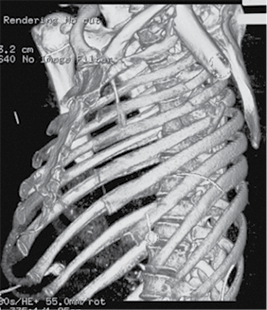

Neurovascular status of the left hand was intact. The patient’s condition was stabilized in the intensive care unit and after 5 days transferred to the Thoracic Surgery Department, where 4 days later a resection of the fifth rib, thoracoscopic removal of the humeral head, and lung decortication were performed.

Figure 2. Subsequent 3D reconstruction